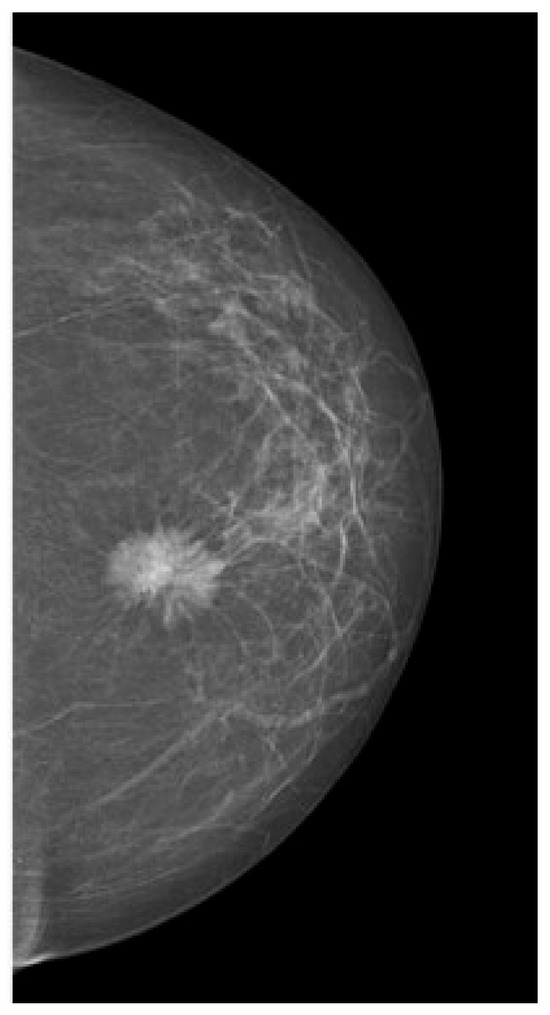

Tumors were classified using the WHO histologic criteria (such as invasive ductal carcinoma, invasive lobular carcinoma, ductal carcinoma in situ, and mixed histology). Age categories were used for analysis. Advanced imaging methods such as breast ultrasound (Figure 2), MRI (Figure 3), mammography (Figure 4), or CT were performed in only a subset of patients, highlighting significant shortcomings in early detection and screening practices within the healthcare system.

Figure 4. Mammography—suspicious spiculated opacities.